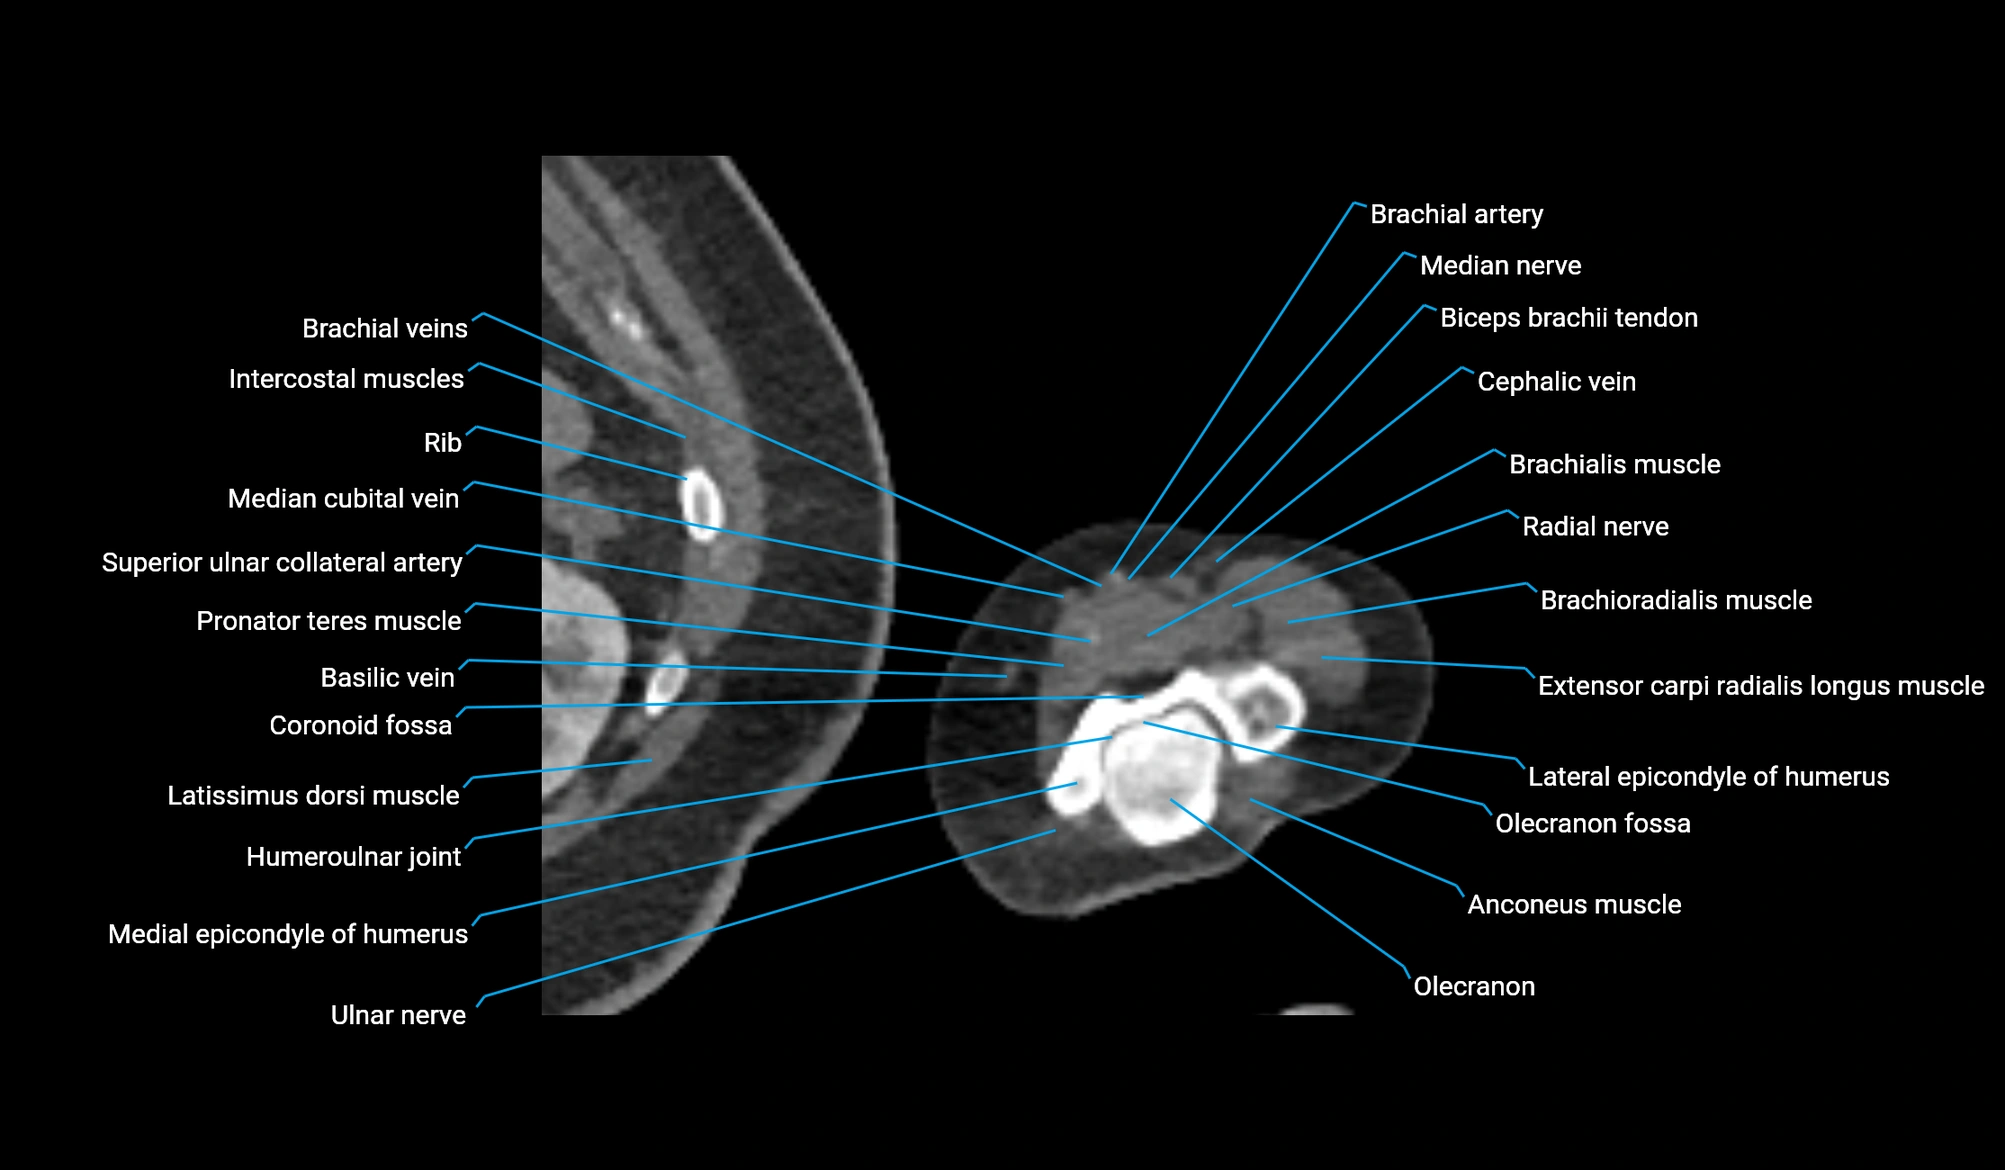

CT image